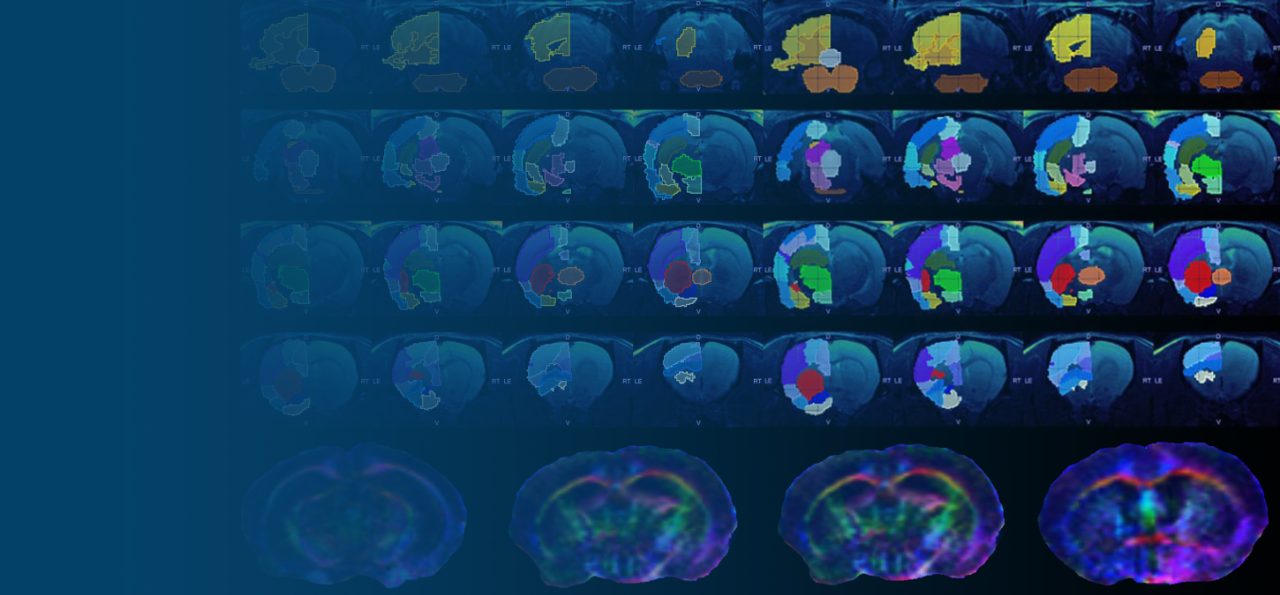

Molecular Imaging uses small amounts of radioactive tracers to image important cellular and molecular processes in living subjects, with applications in oncology, cardiology, neuroscience, immunology, theranostics, drug development and basic life science research. Bruker offers advanced hybrid imaging devices such as modular benchtop PET, SPECT, CT, or hybrid PET/CT, PET/MR and PET/SPECT/CT to help scientists and life science industry to advance their research or business.